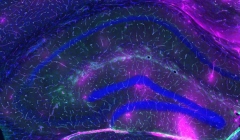

Districare la tau: ricercatori trovano 'obiettivo maneggiabile' per …

30.01.2019 | Ricerche

L'accumulo di placche di amiloide beta (Aβ) e grovigli di una proteina chiamat...